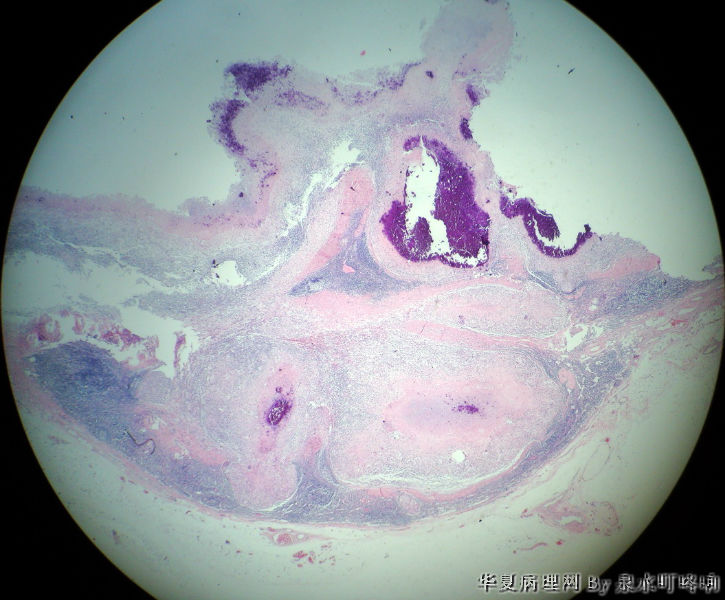

左腋窝肿物

女,3岁,主因左腋窝肿物半年,术中见为肿大淋巴结,淋巴结内有脓液及坏死组织。

大体:灰红色组织一块,大小约4.6×3.5×2厘米,切面可见两个囊性区域,内容乳白色浓稠液体。

肉芽肿性炎(建议做抗酸染色,除外结核)

是淋巴结吧,淋巴结肉芽肿性炎伴坏死,建议做抗酸染色。

肉芽肿性炎,考虑结核伴钙化。